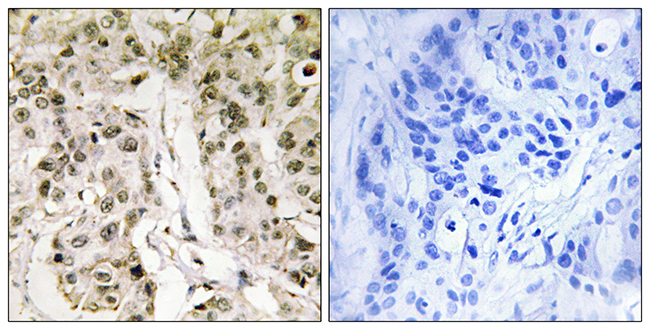

ApplicationsELISA, ImmunoHistoChemistry

ApplicationsELISA, ImmunoHistoChemistry

ApplicationsELISA, ImmunoHistoChemistry

ApplicationsELISA, ImmunoHistoChemistry